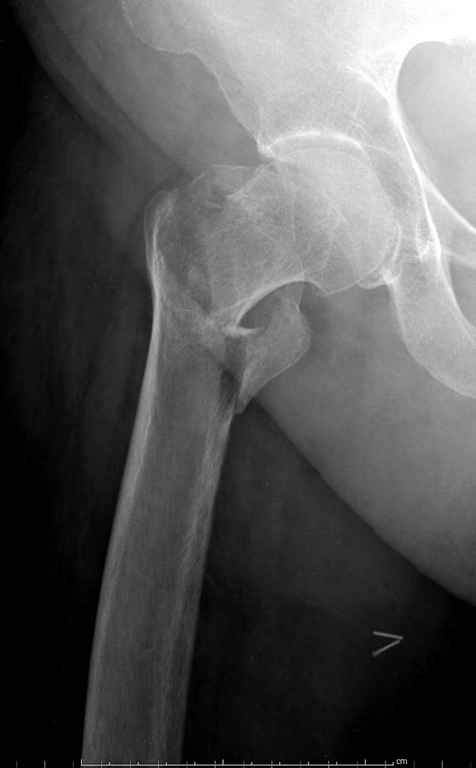

Перелом тут больше подвертельный. Нагрузка без торцевого упора на уровне перелома привела к телескопированию отломков на стержне. Ну и варус небольшой тоже свою лепту внес - если бы его не было, контактирующие латеральные стенки обоих отломков предотвратили бы укорочение, да и срослось бы за пару месяцев. А раз не срослось, упора отломков нет, более слабым местом оказались не нижние винты, а кость в головке и шейке. Так что надо было хотя бы удалить нижние винты до начала полной нагрузки.

Фиксация * reversed obliquity* подвертельных переломов - дело непростое.

На мой взгляд, причиной телескопирования явилось несоответствие диаметра гамма нэйл с диаметром канала подвертельного отдела бедра: обратите внимание на величину протрузии шеечного винта и величину медиализации дистального фрагмента - они одинаковы, смещение или телескопирование фрагментов происходило до того момента, пока гамма нэйл не упёрся в медиальный кортекс и образовалось пространство между латеральным

кортексом и латеральной поверхностью гвоздя.